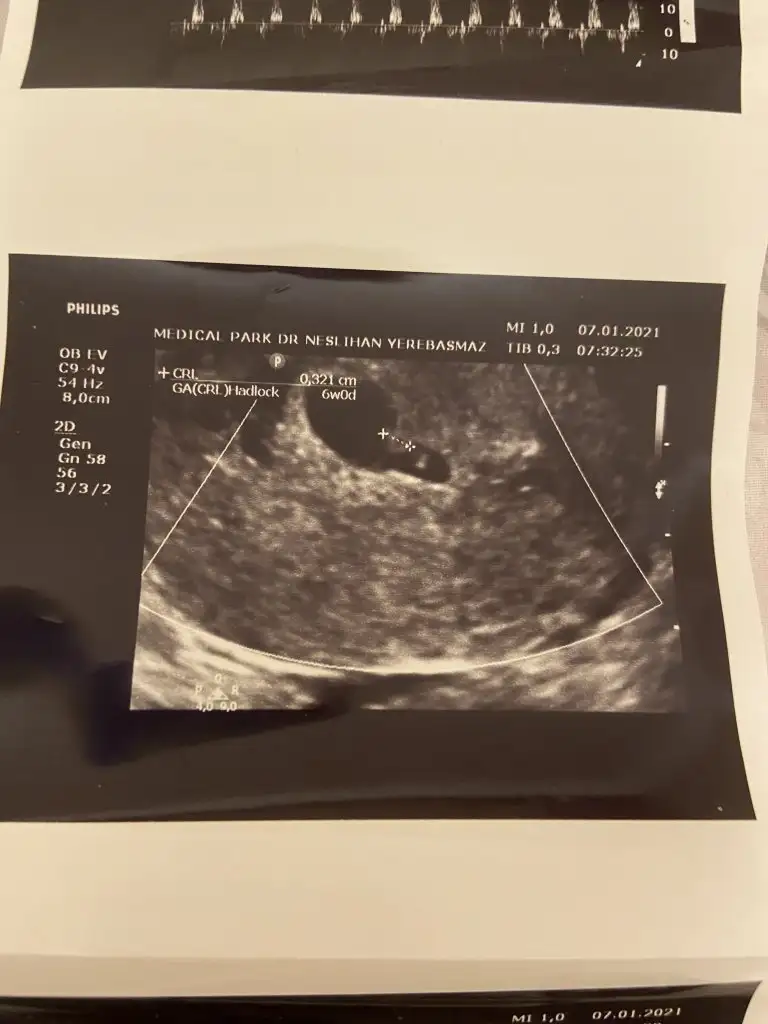

Sanırım kız gibi geldi banaMerhaba benim bebişin cinsiyetinide tahmin edebilir misiniz?Üzerinde haftalar yazıyor . 6 haftalık vajinadan 7 haftalık karından simdiden teşekkür ederim

Evet yalan uYdurma olabilir bizde girgirina yapiyoruz doktor degilimBence bu hepsini yalanlıyor 6 haftalık kız 7 haftalık erkek gibi duruyor. Demekki bebeğin yeri surekli değişiyor teori yalan